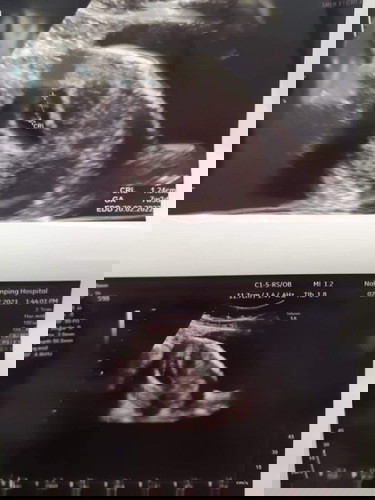

เรียบร้อย ค่ะ ฝากท้อง ซาว เห็นตัวเล็ก ได้ยินเสียงหัวใจเต้น 7สัปดาห์ 3วัน